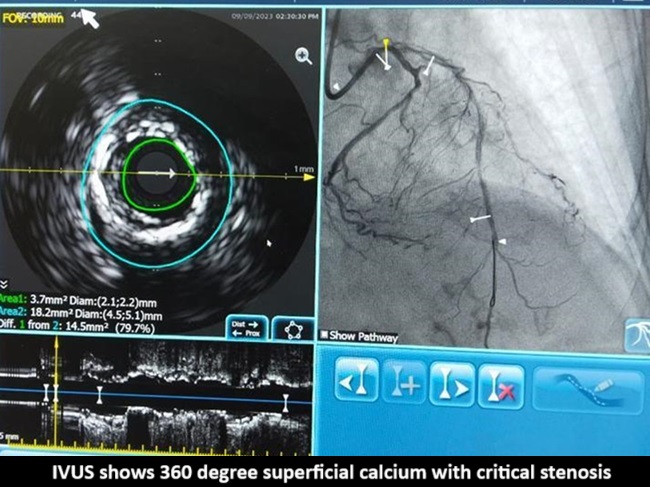

Angiogram shows calcified ostial Lad with critical stenosisLAD is showing calcified lesion from ostial to mid LAD separate origin of LADand LCX

Pre PCI-IVUS showedsuperficial calcium 360 degree at ostium, Predilation was done with 2.5mm OPNballoon and 2.5 wolverine balloon, and 3.5x23mm (Xience Prime company) stentwas deployed at 18atm still there was severe dog boning and Crumpled stent canbe seen in Philips Sync Vision. 3.5x12 IVL done (shockwave company) with 8shocks each of 10 cycles within the crumpled portion Note inner dots containthe region of crumpled stent the way to position IVL for maximum strength. Post-inflationwith IVL, Stent fracture happened and a Clot started forming, another 3.5x23mm (BostonScientific Company) stent deployed in LAD with good result. After 2 hours inCCU patient suddenly developed chest pain and LVF, almost collapsed with BP40/20. Patient was started on inotropes, NIV support and ECG showed new onsetLbbb. It was thought that it could be SAT Gave additional heparin, Started onGp2 B. Fresh echo showed Rwma in LCX territory, new development. Put on IABP andShifted to Cathlab and a check angio done, Final angio with flowing LCX and LADPatient slowly weaned off NIV and IABP in further 3 days